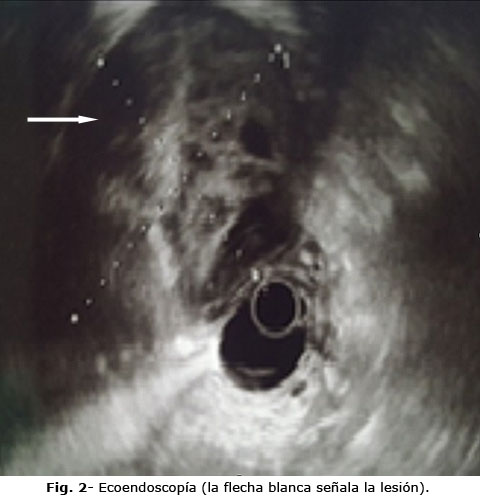

Se realizó ultrasonido endoscópico (ecoendoscopía) en el que se describió lesión heterogénea, poco vascularizada, hipoecoica con zonas hiperecoicas, por calcificaciones y varias áreas anecoicas de contornos bien definidos, excepto en un área de aproximadamente 2 cm en que se pierde la interface del contorno de la lesión con la pared gástrica. Se observa afectada la serosa y muscular propia en ese sitio. La lesión mide 7,1 cm x 5,5 cm sin afectar los vasos, ni las estructuras vecinas (Fig. 2). Se concluye como probable tumor mesenquimal del mesenterio (leiomiosarcoma) o GIST gástrico de crecimiento exofítico.